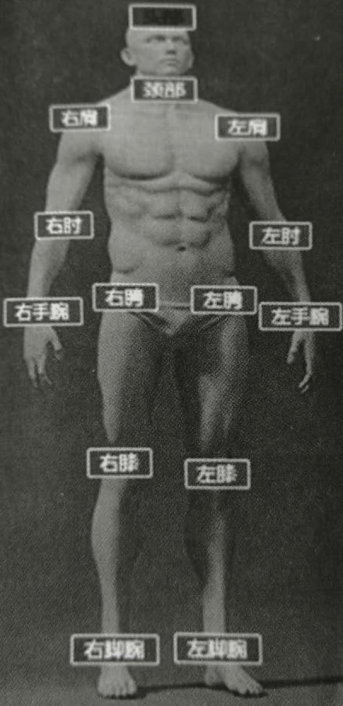

人体标框标注是根据人体不同部位进行标框标注,多用于远程医疗外伤诊断。如图所示,在一张人体图片中对人体各部位进行了标框标注。